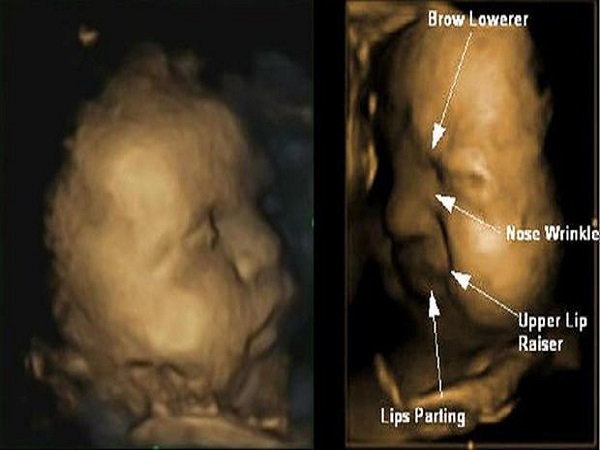

9. அல்ட்ரா சவுண்ட் ஸ்கேன்

சிசுவின் பல்வேறு வளர்ச்சி நிலைகளை பற்றி அறிய இந்த அல்ட்ரா சவுண்ட் ஸ்கேன் பயன்படுகிறது. இது சிசுவின் அளவு, எடை, அசைவுகள், இரத்த ஓட்டம், இருதய துடிப்பு போன்றவற்றை பரிசோதனை செய்கிறது. இந்த ஸ்கேன் முடிவு சரியாக இல்லை என்றால் உடனடியாக மருத்துவரிடன் ஆலோசனை பெற வேண்டியது அவசியமாகும்.